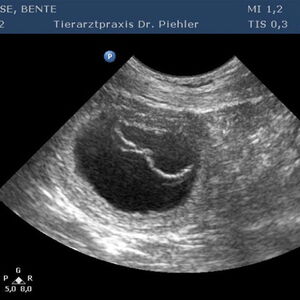

Am 23.03.2020 besuchte uns die Hündin Bente mit ihrem Frauchen Bärbel Loose.

Barolo hat sich dieses Mal in seiner Schnelligkeit übertroffen; kaum war Bente durch die Tür, ging es zur Sache.

Am 24.05.2020 hat Bente 6 gesunde Welpen (3 R | 3 H) zur Welt gebracht.